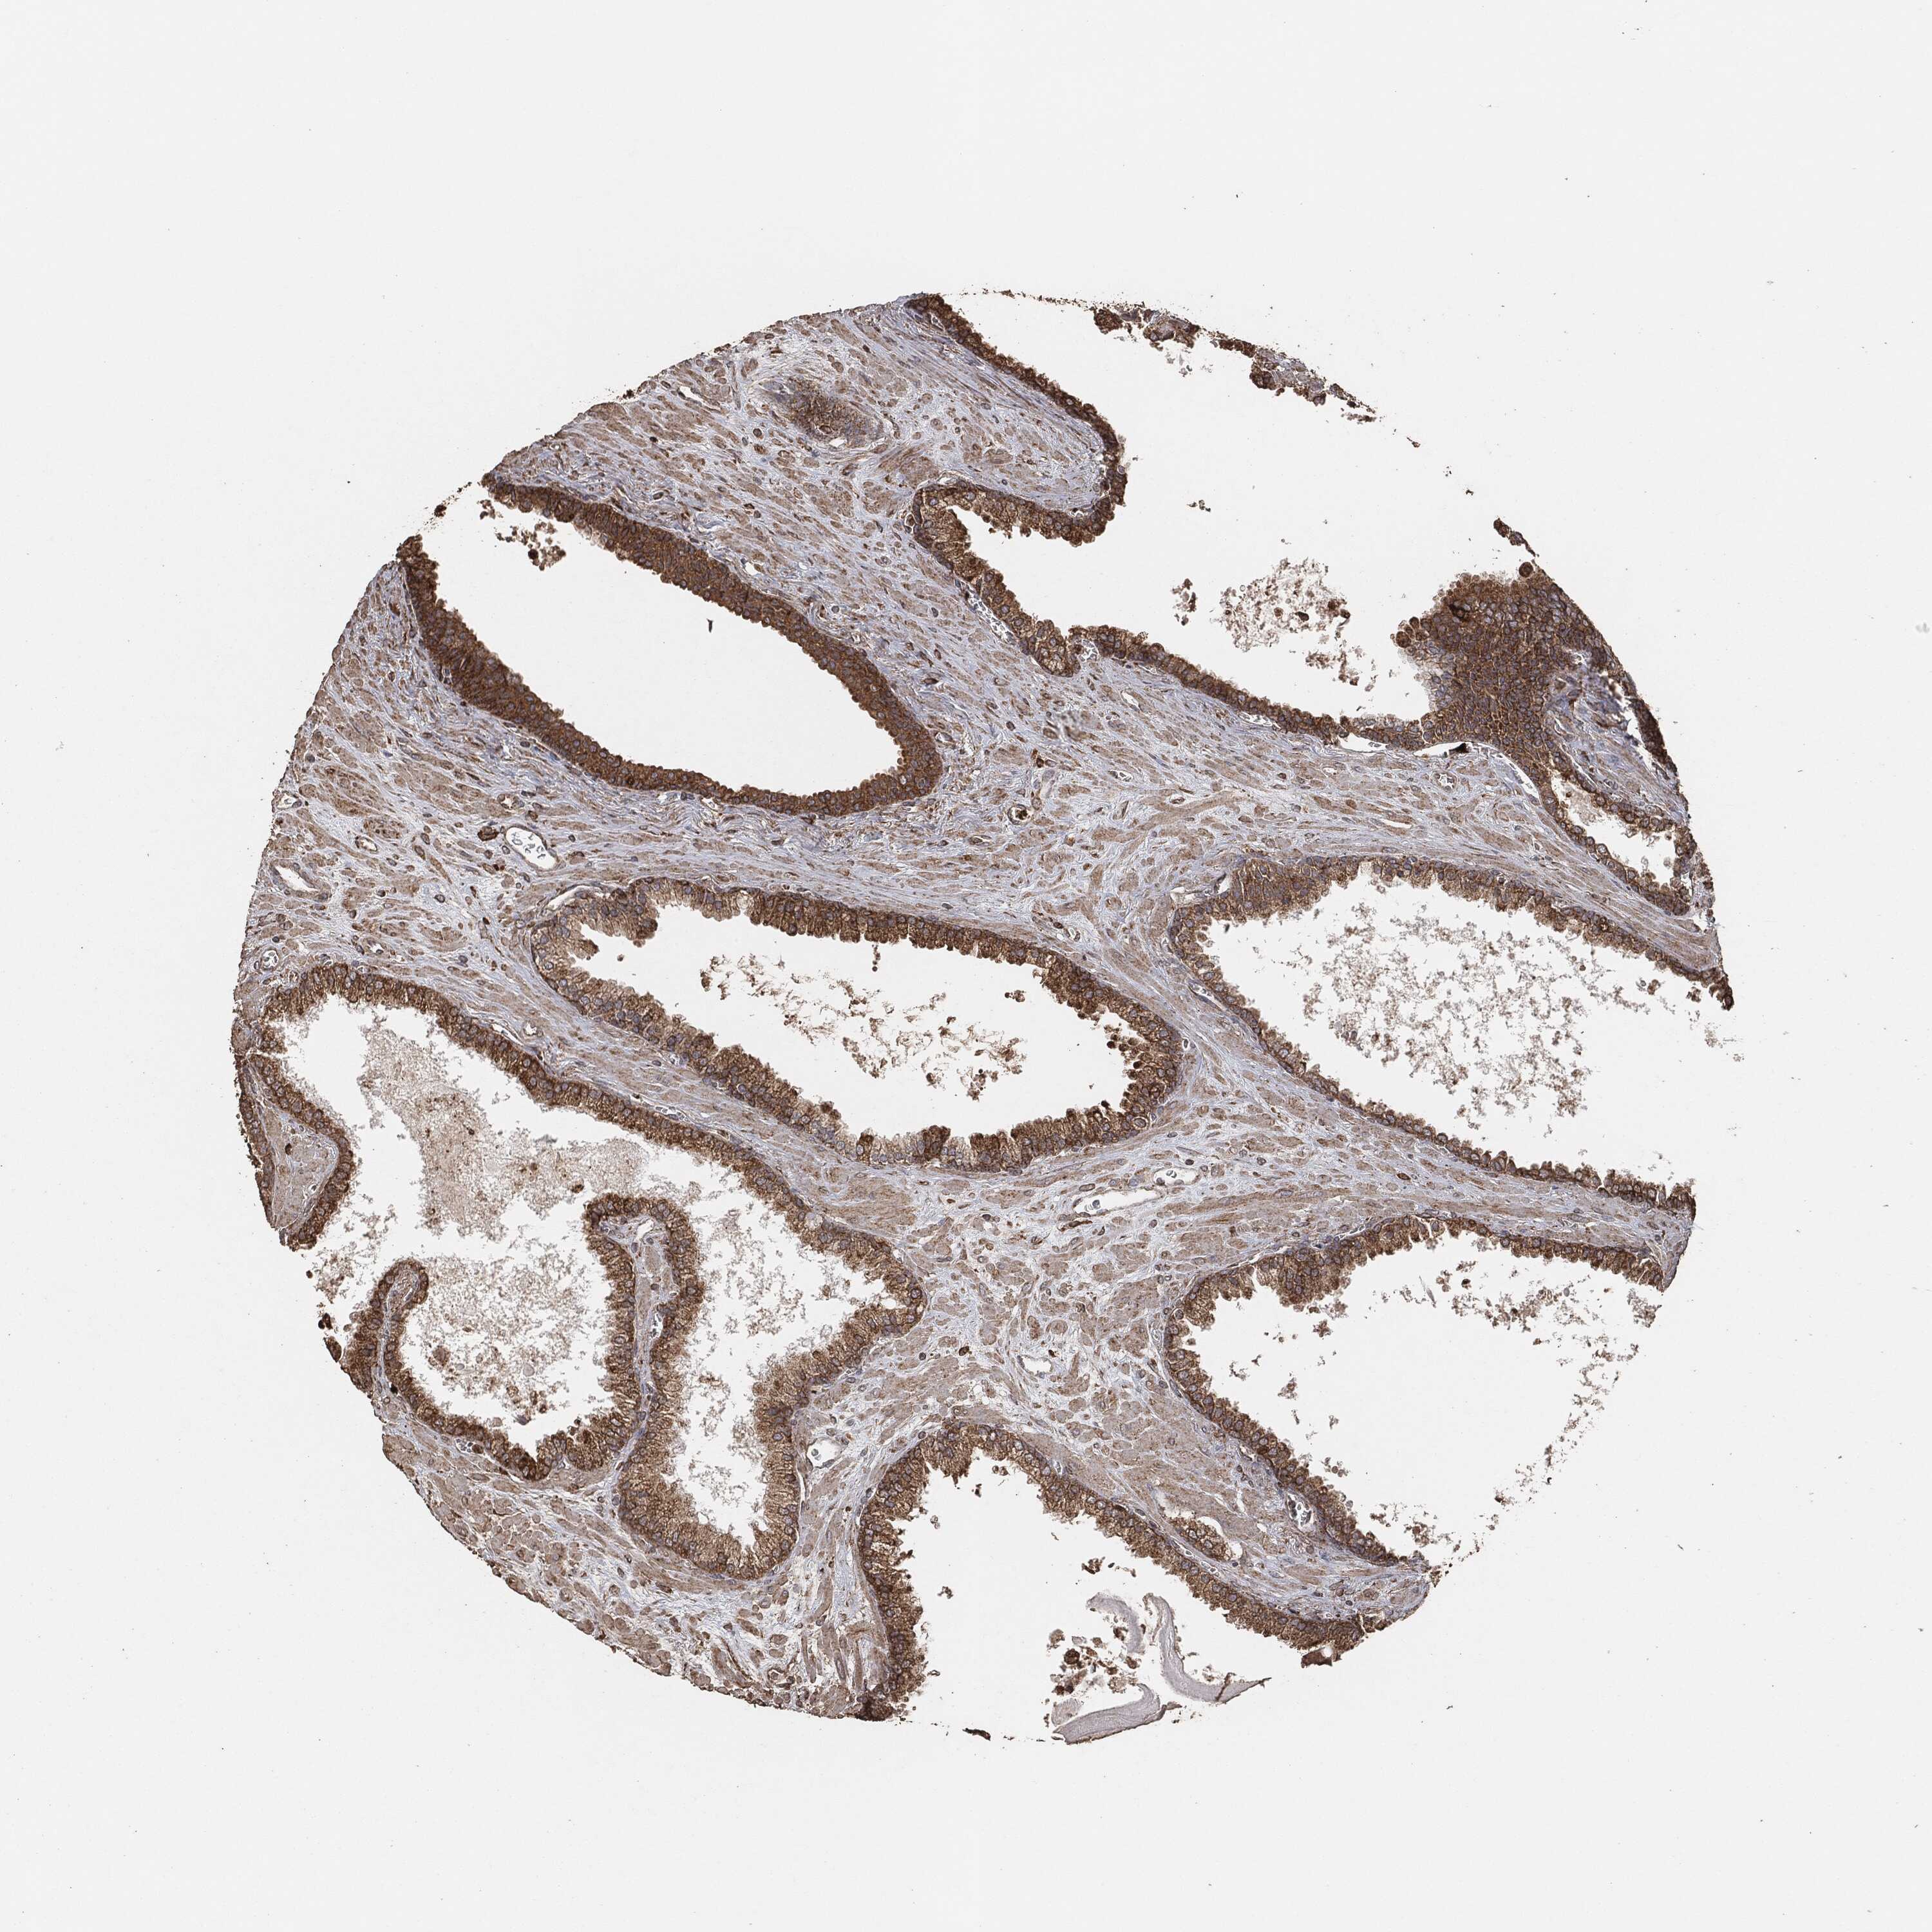

PROSTATE CANCER - Protein expressioni

A mouse-over function shows sample information and annotation data. Click on an image to view it in a full screen mode. Samples can be filtered based on level of antibody staining by selecting one or several of the following categories: high, medium, low and not detected. The assay and annotation is described here.

Antibody stainingi

Antibody staining in the annotated cell types in the current human tissue is reported as not detected, low, medium, or high, based on conventional immunohistochemistry profiling in selected tissues. This score is based on the combination of the staining intensity and fraction of stained cells.

Each image is clickable and will lead to virtual microscopy that enables deeper exploration of all samples and also displays staining intensity scores, fraction scores and subcellular localization as well as patient and tissue information for each sample.

Adenocarcinoma, Medium grade

Adenocarcinoma, Low grade

Adenocarcinoma, High grade

Adenocarcinoma, NOS